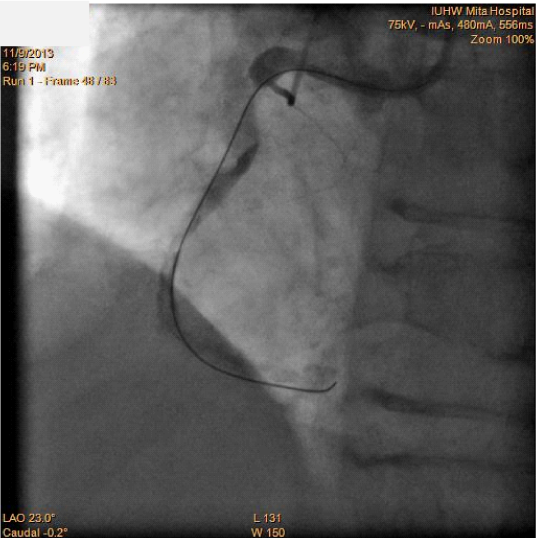

Figure 3 Successful passage of the ULTIMATEbros 3®guidewireinto the distal portion of the right coronary artery.